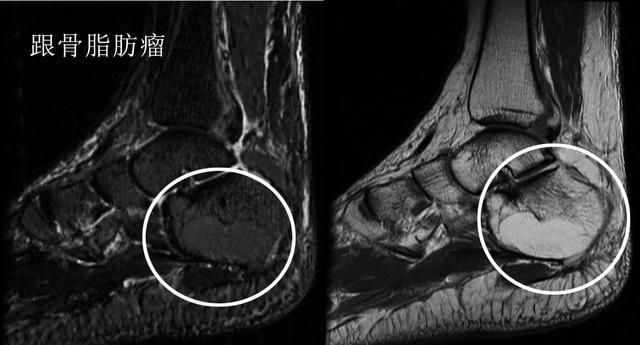

足跟痛的常见原因主要还是见于足底的筋膜炎以及跟腱炎,但这不代表是所有诱发足跟痛的原因。今天比较详尽和大家介绍了一下诱发跟痛症的其他多种原因,限制于篇幅有一些特别少见的疾病并未再给大家展开,比如跟骨脂肪瘤等疾病。

足跟疼痛教你一招百试百灵,早起落地脚疼